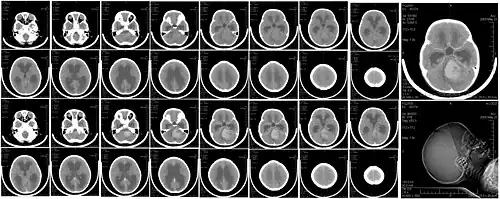

Głowa

Tomografia komputerowa jest obecnie podstawowym badaniem obrazowym pozwalającym na uwidocznienie struktur śródczaszkowych. Powinna być wykonana jak najszybciej w przypadku udaru mózgu w celu zróżnicowania pomiędzy udarem niedokrwiennym i krwotocznym. Pozwala też wykryć obecność guza śródczaszkowego albo krwiaka pourazowego.